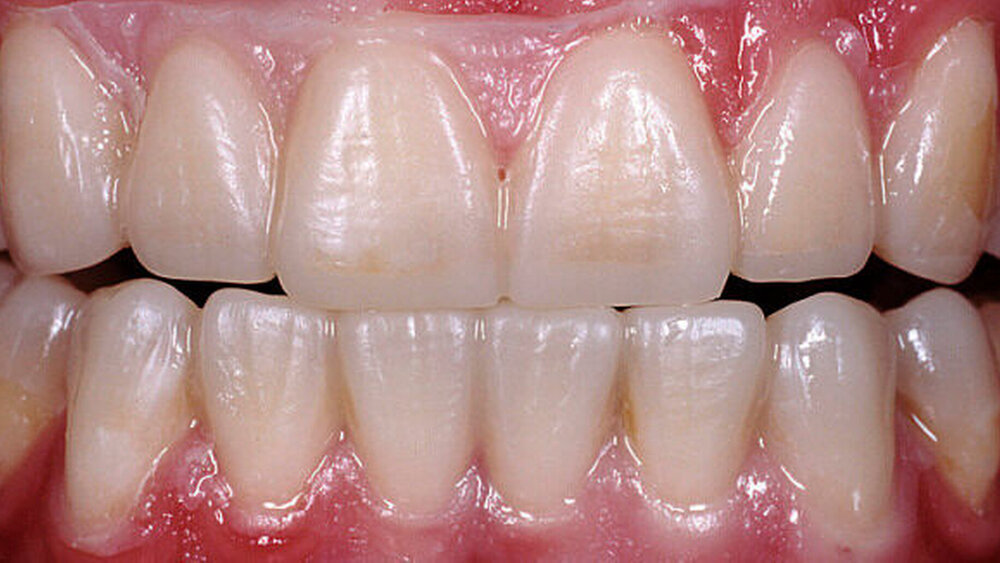

Nach einer klinischen Funktionsanalyse (Abbildungen 1 und 2) werden Situationsmodelle hergestellt und diese anhand einer arbiträren Scharnierachsbestimmung und eines Zentrikregistrats im Artikulator montiert. Die für die spätere Versorgung funktionell und ästhetisch ideale Vertikaldimension wird durch ein analytisches Wax-up eingestellt (Abbildung 3). Dieses wird in eine diagnostische Schablone (Tiefziehfolie) für eine „ästhetische Evaluierung“ durch den Zahnarzt und den Patienten überführt. Dazu kann die Schablone mit niedrigviskösem Komposit gefüllt und reversibel auf die mit flüssiger Vaseline isolierten Zähne gesetzt werden. Findet dieser Restaurationsvorschlag die Zustimmung des Patienten, wird im zahntechnischen Labor eine in der Höhe und in der Bisslage dem Wax-up entsprechende Repositionsschiene mit Front-Eckzahn-Führung angefertigt. Diese Schiene sollte circa drei Monate möglichst permanent getragen werden. Diese „funktionelle Evaluierung“ dient dazu zu prüfen, ob der Patient die neue Bisslage beschwerdefrei toleriert [Edelhoff et al., 2013; Harper, 2000; Rivera-Morales et al.,1992].

Wird die Bisslage vom Patienten beschwerdefrei akzeptiert, kann die Übertragung der Situation entweder direkt in vollkeramische Restaurationen oder zunächst in CAD/CAM-gefräste, langzeitprovisorische Repositions-Veneers oder -Onlays aus Hochleistungs- polymer – meist PMMA-Material – erfolgen (Abbildung 4). Für die Konstruktion können die Datensätze der Wax-up-Modelle verwendet werden. Die Table Tops werden gewöhnlich mittels Adhäsivtechnik auf natürlichen Zähnen und Kunststofffüllungen befestigt, können allerdings auch bei entsprechender Vorbehandlung (intra-orales Anstrahlen) auf metallischen und keramischen Restaurationsoberflächen eingesetzt werden [Bertolotti et al., 1994]. Da die neue Bisssituation nun permanent inkorporiert ist, können sich die neuronalen Bewegungsmuster besser adaptieren. Um künftig funktionelle Beschwerden nach definitiver Rekonstruktion der vertikalen Kieferrelation möglichst auszuschließen, sollte diese semipermanente Phase für etwa sechs bis zwölf Monate beibehalten werden.